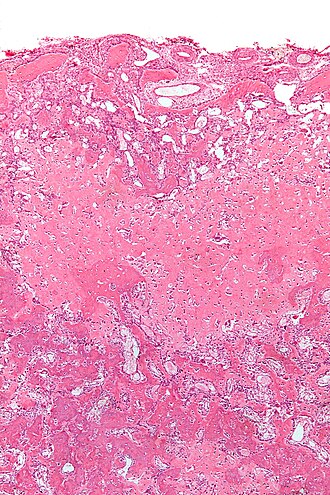

Template:Px Osteoblastoma. H&E stain. | |

| LM | anastomosing bony trabeculae with variable mineralization, osteoblastic rimming, no nuclear atypia of osteocytes |

- Anastomosing bony trabeculae with:

- Osteoblastic rimming.

- Cells line-up at edge of bone.

- Histomorphologically near identical/indistinguishable from osteoid osteoma.[5]